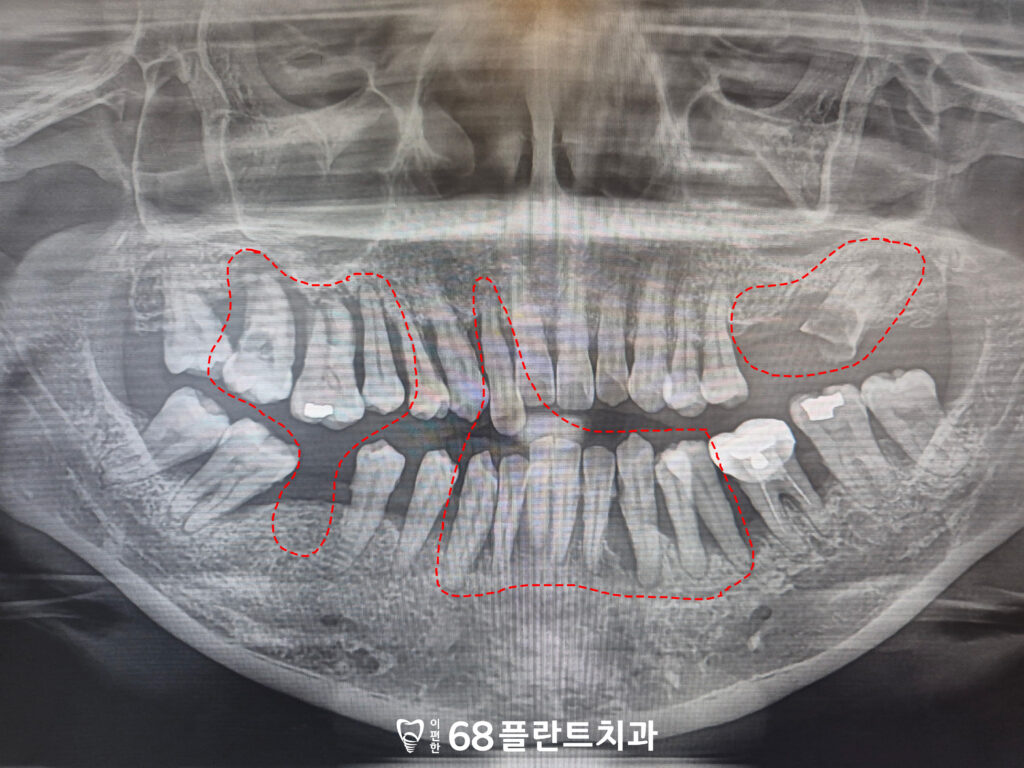

23.04.05

위 환자분은

전체적인 잇몸 염증으로 인해

치아가 흔들리고 불편하다며

철산동치과 이편한68플란트에

내원해 주셨습니다.

확인해 보니,

치주염으로 인해 잇몸뼈가

광범위하게 소실되고

그로인해 치아를 잡아주는 뼈가 부족하여

치아가 흔들리고 있었습니다.